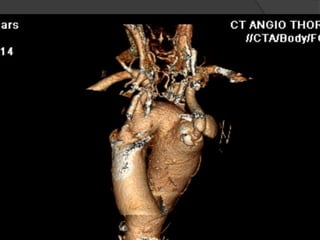

Cas 1

 CTA Pre-opératoire:

 Artere sous clavière aberrante droite

○ Origine a partir de l’aorte thoracique descendante,

distal a l’artere sous-clavier gauche

○ Trajet derriere l’œsophage et la trachée

 Diverticule de Kommerell a l’origine de l’artere

sous-claviere aberrante droite (diamètre 4.6 cm)

 Origine commune des artères carotidiennes

(CCA)

 Artere vertébrale droite dominante qui origine de l

artere sous-clavier aberrante droite

 Aucuns autres anévrismes ou sténoses